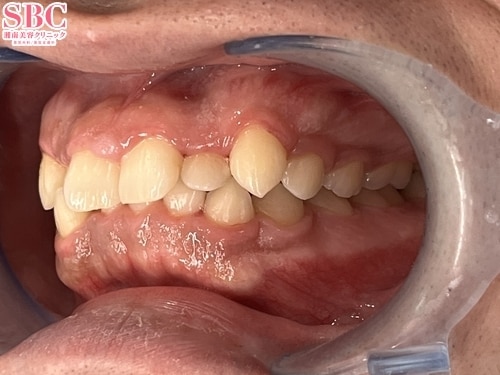

No.339657【美容歯科】【れいな先生】噛み合わせも見た目も改善!マウスピース矯正で変わるんです【マウスピース矯正】

施術前

がたつきと噛み合わせが気になる

施術後15ヶ月後

綺麗に整い、上手く噛めるようになりました

こちらの症例はインビザラインフルの症例になります

親知らずのみ抜歯を行いました。

前歯は生まれつき小さい矮小歯ですので、天然のままですとこのような仕上がりになります

ご希望の方には被せ物などで整える治療も行っております